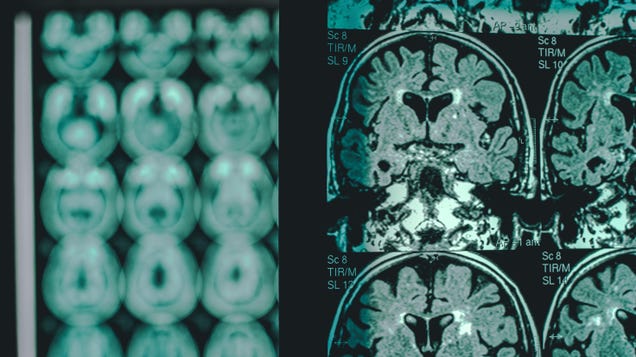

On Thursday, the Food and Drug Administration made a decision that’s likely to have a major impact on the landscape of Alzheimer’s disease research. The agency issued a full-throated traditional approval of the drug Leqembi, developed by the companies Eisai and Biogen. The drug is the first of its class to receive…